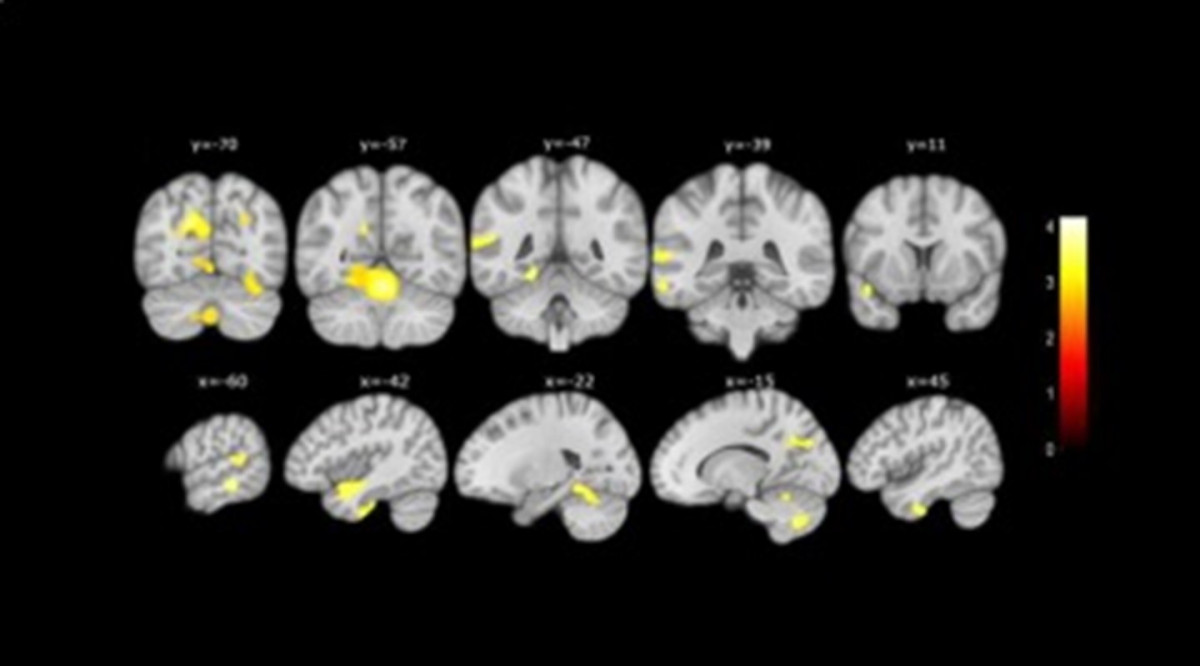

Además, gracias a la resonancia magnética realizada a un subgrupo de participantes, los investigadores también descubrieron que las personas que presentaban más de tres características asociadas a las quejas presentaban una mayor atrofia cerebral que los otros participantes con quejas pero con menos características asociadas.

MENOR VOLUMEN

En concreto, observaron un menor volumen en áreas cerebrales que se afectan en la enfermedad de Alzheimer, como son el hipocampo, el lóbulo temporal, el cerebelo y el precúneo.

Por otro lado, los análisis de neuroimagen y los test cognitivos también revelaron que las personas con quejas de memoria cuyos allegados confirmaron estas quejas, obtenían peores resultados cognitivos y también presentaban un volumen inferior en áreas cerebrales relacionadas con la enfermedad.